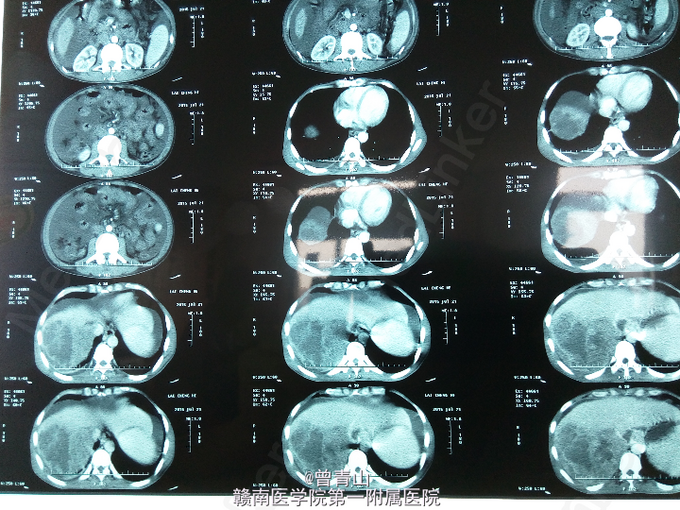

查体:腹部稍膨隆,硬,全腹可及轻度压痛及反跳痛,肝肋下右锁骨中线处4cm处可触及,脾脏未触及,肝区叩击痛阳性,移动性浊音阳性,肠鸣音弱,未见肝掌及蜘蛛痣。辅助检查:血分析:红细胞(仪器法)3.99*10^12/L,中性细胞比率85.91。甲胎蛋白(化学发光)104517ng/ml。凝血功能:(AT3)AT-Ⅲ51.3%,凝血酶原时间14.2s,D-二聚体4.84mg/L。尿分析:蛋白质1+,酮体1+,白细胞55.6/ul,管型20.81/ul,浊度1+。大便常规正常。肝功能:天门冬氨酸氨基转移酶(速率法)47U/L,总蛋白(双缩脲法)55.8g/L,白蛋白(溴甲酚绿法)30.3g/L,总胆红素(酶法)22.9umol/L,直接胆红素12.6umol/L。乙肝表面抗原>>225.000ng/ml,乙肝核心抗体>>4.020PEIU/ml。上腹部增强CT提示:肝增大,肝右叶见10.0*12.5cm大小低密度肿块,增强扫描早期呈不均匀强化,门静脉期与延迟期呈低密度,门静脉主干与左右分支内见低密度充盈缺损,门静脉周围见多发性迂曲血管影。

患者目前诊断:肝右叶原发性肝细胞肝癌并门静脉癌栓形成。处理:给予护肝、补液、营养支持等对症处理。由于患者肝癌并门静脉癌栓形成,一般情况较差,在我院的技术尚不能给患者行手术治疗,也无其余更好的治疗方法,建议去肝胆外科知名度高的医院就诊。